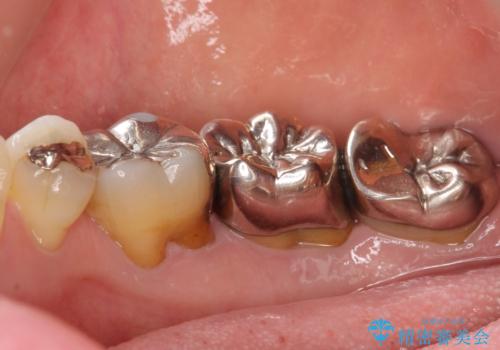

精査したところ右下の奥歯も歯周病により保存不可能な状態でした。

なるべく予算を抑えたいとのご希望から、上顎は入れ歯、右下臼歯部はインプラントによる治療を行いました。

被せ物の種類:メタルボンドクラウン エコノミー